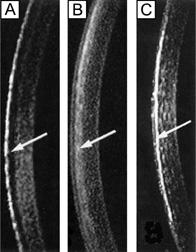

Several surgical procedures have also been developed to permanently alter the curvature of the cornea, thereby reducing nonpathologic refractive errors. The procedures most commonly performed today include laser-assisted in situ keratomileusis (LASIK), photorefractive keratectomy (PRK), and astigmatic keratotomy (AK). LASIK and PRK are surgical techniques that use an excimer laser (193 nm) to ablate the anterior corneal stroma with submicron accuracy and create a new refractive surface. LASIK is different from PRK in that it involves a mechanical or laser created lamellar keratectomy step before the excimer ablation step, which is applied to the underlying residual mid-stromal bed. PRK ablation directly occurs on the surface of the cornea (Bowman's layer and anterior stroma). Both procedures have been used on myopic and hyperopic eyes with up to a mild degree of astigmatism and produce similar visual outcomes. AK is an incisional keratotomy technique that cuts up to 90% depth arcs in the peripheral cornea using a scalpel to reduce astigmatism by flattening the cornea in the visual axis over the area of the cut. AK is usually performed in association with cataract surgery.